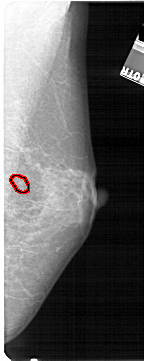

FILE: A_1327_1.RIGHT_MLO.OVERLAY

TOTAL_ABNORMALITIES 1

ABNORMALITY 1

LESION_TYPE CALCIFICATION TYPE PLEOMORPHIC DISTRIBUTION CLUSTERED

ASSESSMENT 4

SUBTLETY 4

PATHOLOGY BENIGN

TOTAL_OUTLINES 1

BOUNDARY